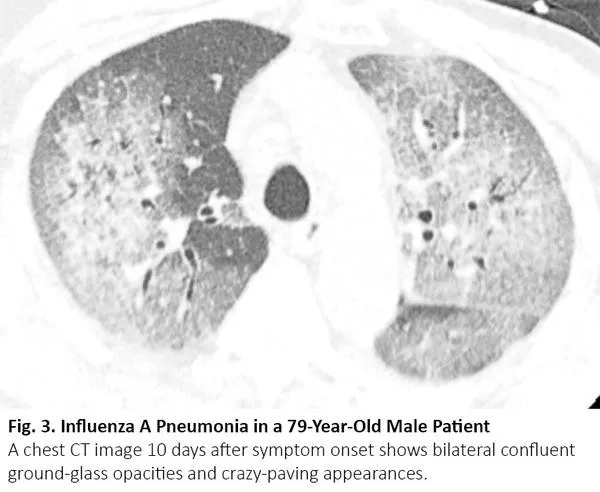

COVID-19患者的肺部CT的典型表现为双侧多发磨玻璃样影,好发于肺周3(图1)。61%~72%的COVID-19患者在症状出现后1周左右有典型CT表现,而非COVID-19患者只有不到10%人群有此类表现。4,5

图1. COVID-19患者胸部CT的典型表现

COVID-19的胸部CT可伴有局部的实质化和网状阴影(铺路石征影像表现)或其他组织性肺炎的表现,如反晕征。17% - 20%的COVID-19患者的CT与各种感染性、非感染性肺部疾病(如超敏性肺炎、肺孢子虫肺炎和弥漫性肺泡出血)难以区分(图2)。